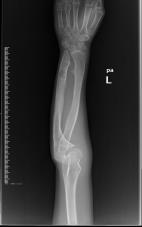

桡骨陈旧性骨折骨不连、畸形

儿童陈旧性孟氏骨折

术前前臂侧位片

术后肘关节侧位片

术后1个月肘关节侧位片

儿童陈旧性孟氏骨折,术前桡骨小头陈旧性脱位,经截骨矫形治疗后1个月,桡骨小头已复位,患儿肘关节屈伸功能(1-2图),前臂旋转功能(3-4图)正常